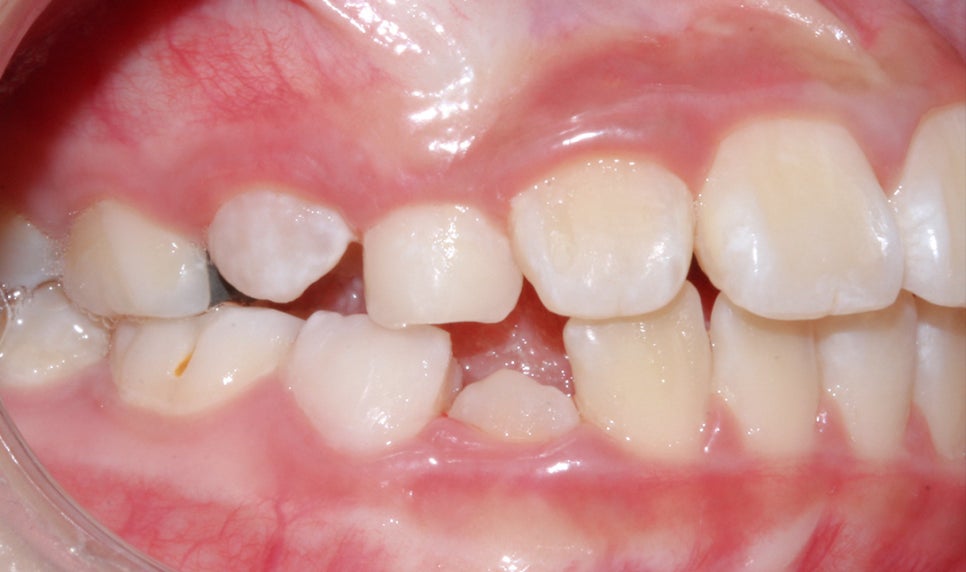

환자분의 상태를 살펴보면

치아가 날 공간이 부족하거나 치아가 나오는 방향에서

앞니가 앞으로 나오고 다른 치아가 기울어지면서

거꾸로 물리는 현상이 발생한 걸로 보여요.

어린이 치아교정 상태

투디 치과(2D 치과)

Before / after

상하악 Clippy-C (클리피씨) 전체 교정